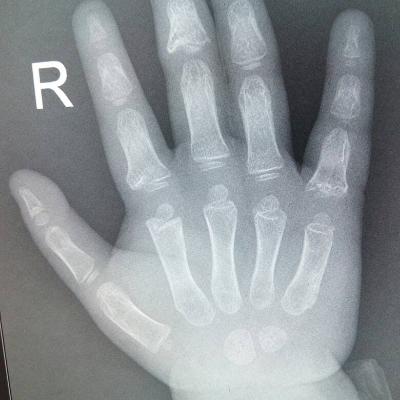

患者女,40岁,医院职工家属。B超体检时发现肝肾间多发囊性占位性病变。行腹部平扫示:右肾上腺区囊性占位,有分割和钙化点,右肾受压下移。诊断意见:右肾上腺囊腺瘤可能性大,建议进一步检查明确。后到市级医院检查并切除手术,病理切片考虑肾上腺囊肿。今腰部不适复查CT片。